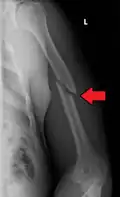

A transverse fracture of the humerus shaft -

A spiral fracture of the distal one-third of the humerus shaft -